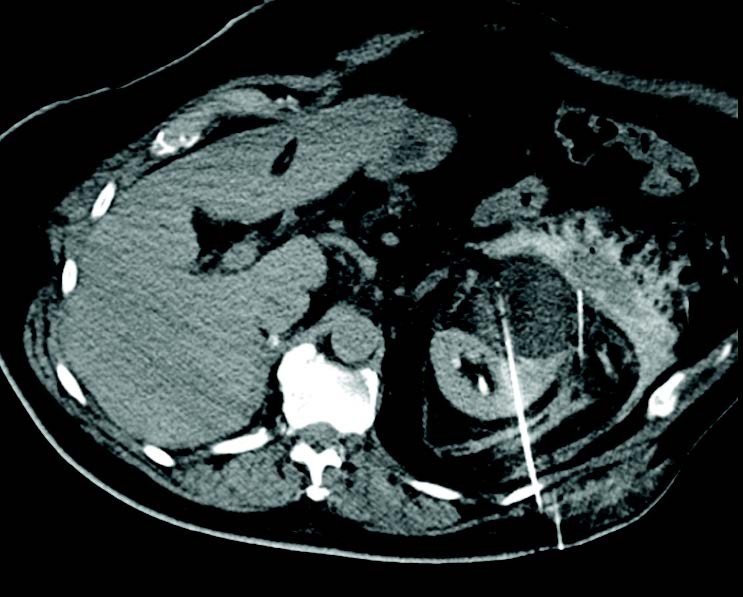

Crioablación de tumor renal de 7 cm después de nefrectomía contralateral previa

Un hombre de 78 años presentó un CCR multifocal en el riñón derecho con invasión venosa y un CCR convencional de células claras de 7 cm en el lado izquierdo. El tumor derecho fue tratado con nefrectomía y el tumor izquierdo fue tratado con crioablación 3 meses después de la nefrectomía. Se utilizó hidrodisección para proteger las estructuras adyacentes y se usaron 7 agujas IceRod™ 1.5 PLUS para el tratamiento. No se reportaron eventos adversos y las imágenes de seguimiento temprano del riñón izquierdo confirmaron una ablación adecuada.Alex King, MD | Hospital Universitario de Southampton | Southampton, Reino Unido